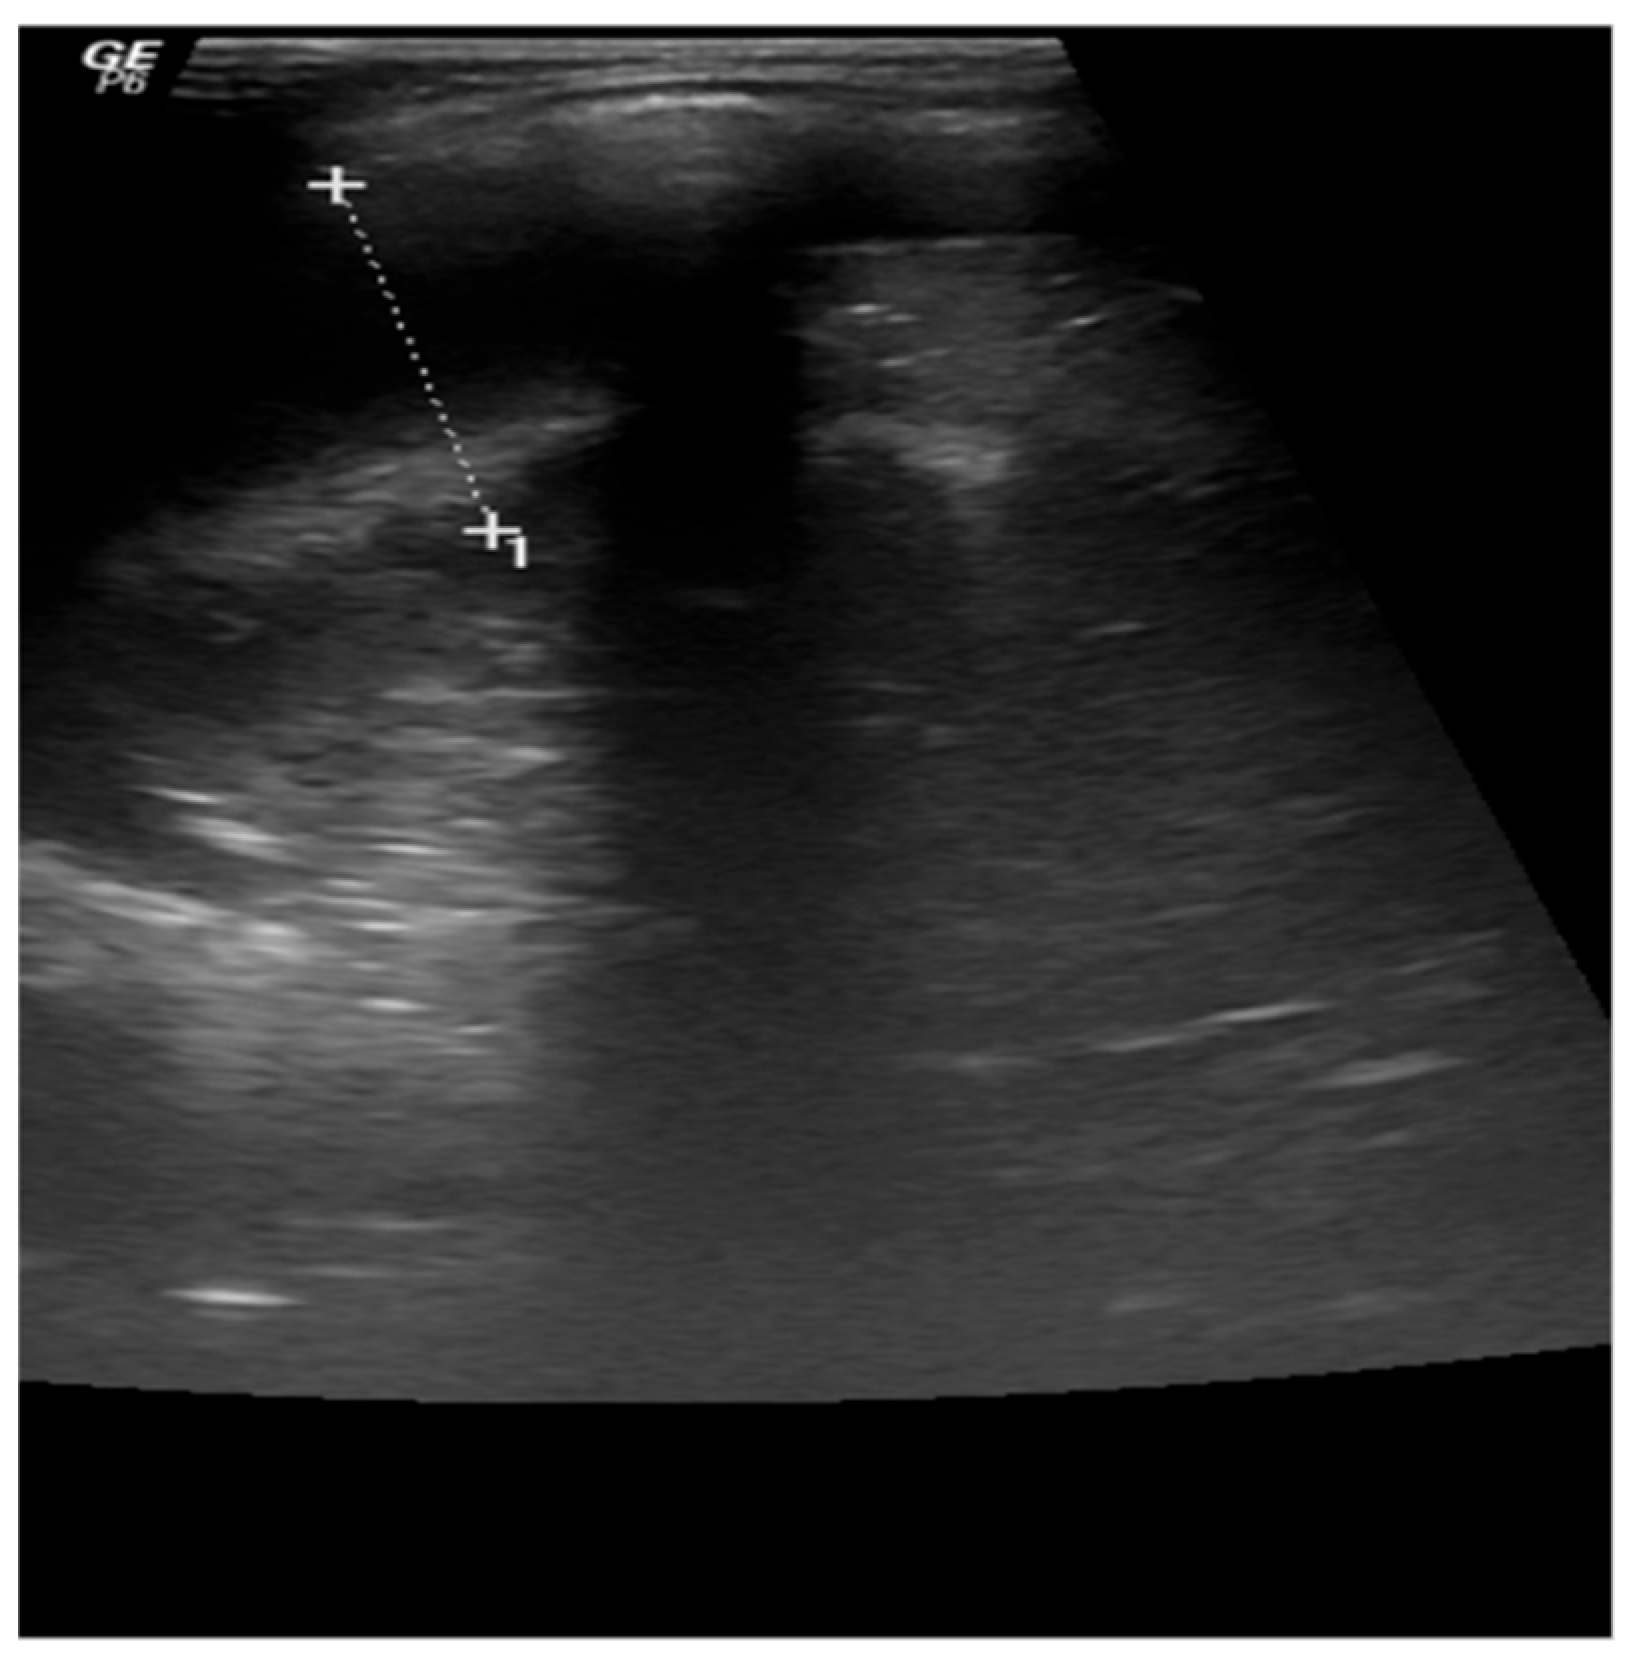

3.1. Case 1

3.2. Case 2